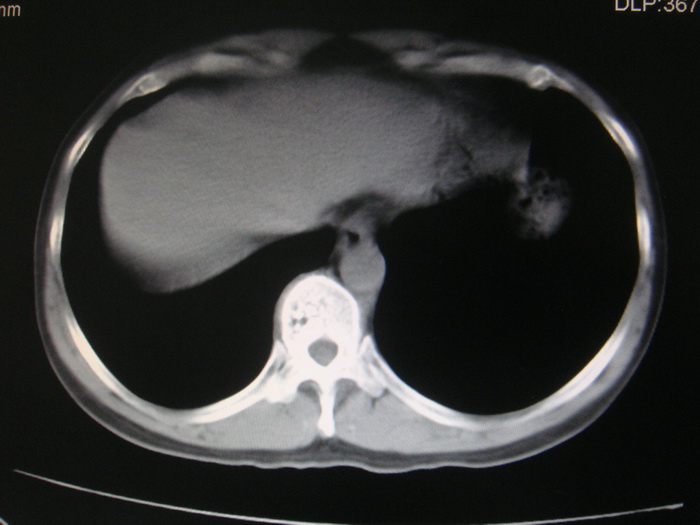

标题: CT28366:男性,45岁,偶尔发现右颈部肿块行胸部CT扫描。 [打印本页]

男性,45岁,偶尔发现右颈部肿块行胸部ct扫描。

两肺多发结节灶及纵膈淋巴结肿大考虑为转移

两肺多发性转移瘤,纵隔淋巴结转移。

两肺多发性转移瘤,纵隔淋巴结转移。食道中上段管壁似乎增厚,作相关检查。

两肺多发性转移瘤,前上纵隔淋巴结转移。